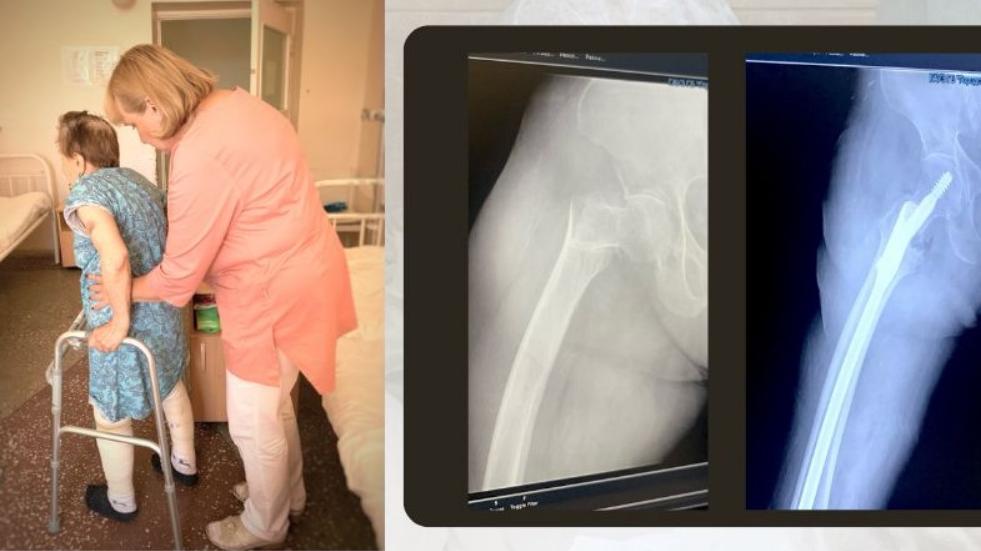

Шейка Бедра Фото Симптомы

Шейка Бедра Фото Симптомы 113 фотографий